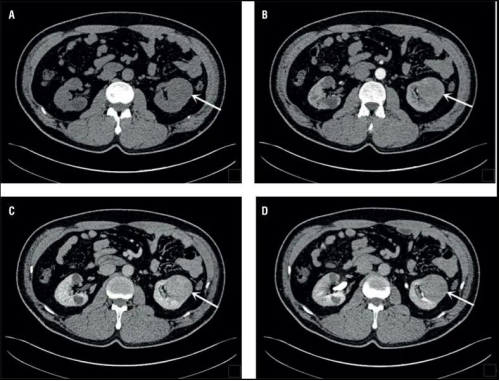

CT圖像舉例

原理簡介:CT檢查相當(dāng)于把人體切成一定間距的小段,間距可以是0.25cm、0.5cm、1cm等等,切完以后可以在圖像上看到每一段橫切面的狀態(tài)。不同的切面呈現(xiàn)不一樣的臟器,通過掃描把人體各個部位的器官和結(jié)構(gòu)拉開,使我們可以看得非常清晰。

優(yōu)點:可以斷層看,經(jīng)后期處理可以顯示更多信息;